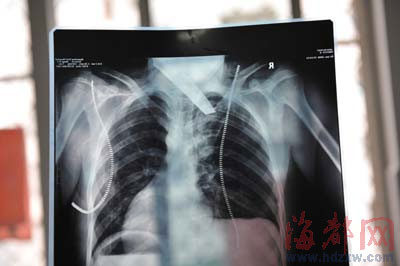

前晚,在第一醫(yī)院急救室,經(jīng)過4個(gè)多小時(shí)的搶救,醫(yī)生將匕首從小勇身上取出,發(fā)現(xiàn)這把匕首的刀尖扎斷了1厘米。由于小勇肺部被刺中,昨天上午,醫(yī)生再次進(jìn)行了3個(gè)多小時(shí)的手術(shù),切除了受傷的部分肺,直到下午,小勇才挺過來!巴α艘灰梗F(xiàn)在總算醒了過來!睏钆恳灰箾]睡,守在手術(shù)室外7個(gè)多小時(shí),生怕兒子再醒不過來。不過,由于傷勢(shì)嚴(yán)重,小勇目前戴著氧氣呼吸,仍未脫險(xiǎn)。